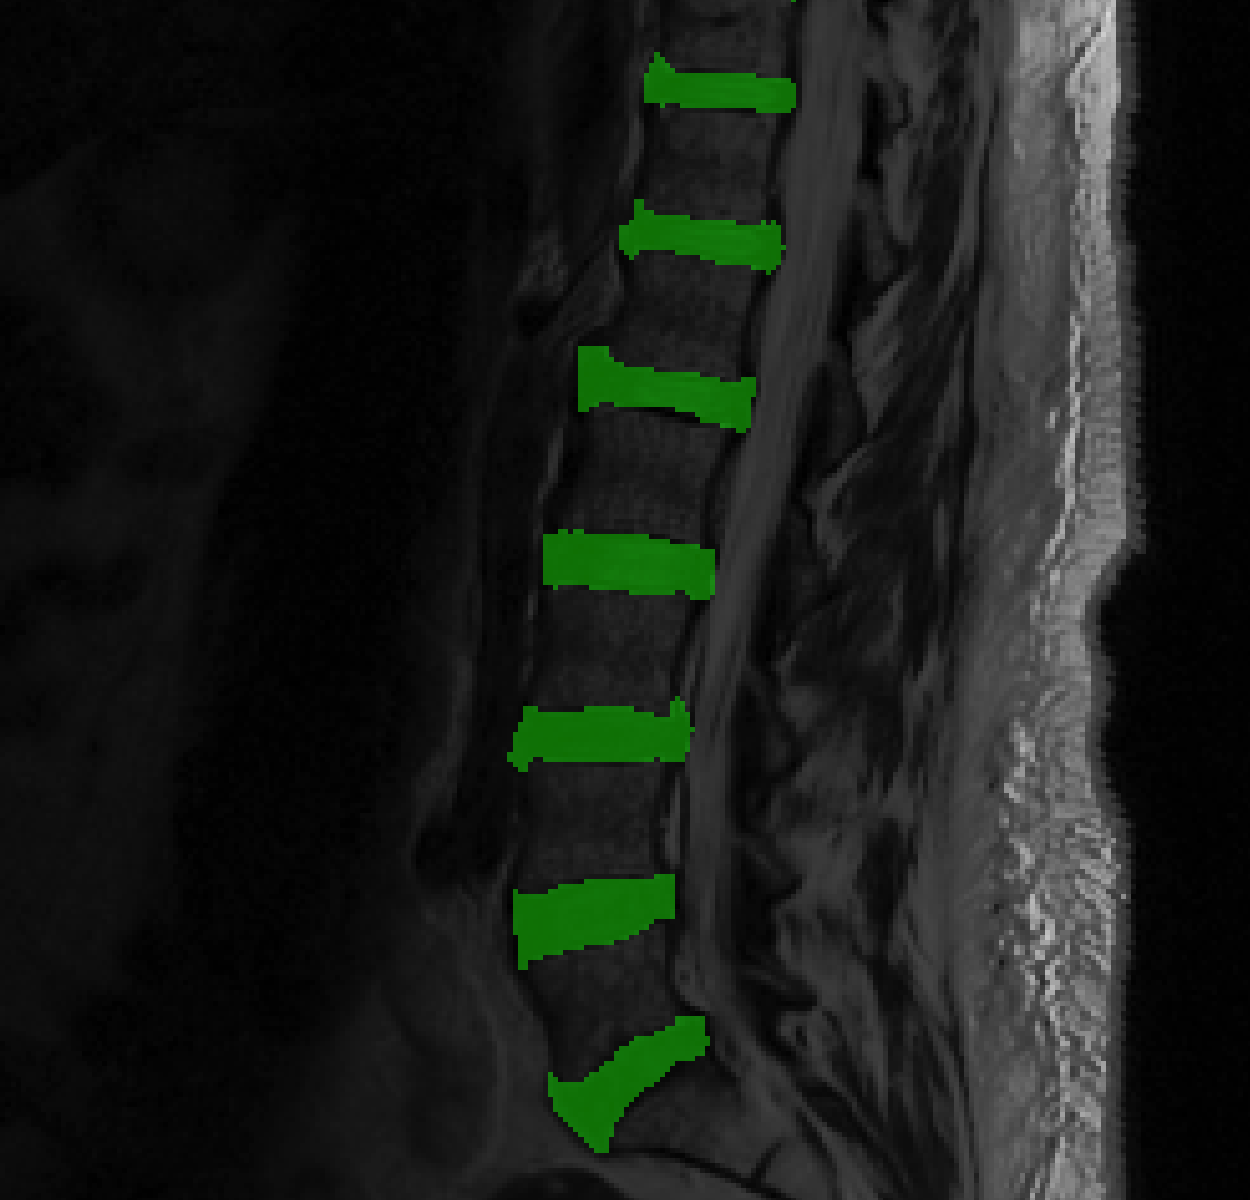

We used 40 scans for validation, none of which were in the training set to generate figures 6 and 7. Each of the 30 models trained, were used to segment the validation cohort of 40 cases, and Dice scores comparing algorithmic segmentations to human generated segmentations were recorded. Mean Dice scores for the entire validation datasets, generated by each model are presented in Table 2. To give the reader a qualitative assessment of how powerful extreme augmentation is, we show in figure 5, a mid-sagittal slice with segmentation overlays generated by models at 50x data augmentation. Dice scores, at augmentation levels 5x, 20x and 50x, for all training sets, are shown in figure 6. Likewise, figure 7 shows Dice scores generated by holding the data set size constant, and varying the level of augmentation. Only results from training datasets of sizes 1, 5 and 9 are shown.

Figures 3 and 4 along with table 1 indicate that more augmentation leads to lower training error, as does training with larger datasets. Figures 5 and 6 alongside Table 2, confirm this trend in the validation dataset. Thus, we may conclude that, for a given training dataset, a greater degree of augmentation leads to improved generalization accuracy. This is expected, given the long history of augmentation. What is surprising is how well augmentation can work. The top row of figure 3 (and figure 6) show that at 5x augmentation our trained model struggles to ‘learn’ how to segment disks. Bottom rows of the same figures show that with 50x augmentation, the situation is largely rectified. Perhaps, the most startling conclusion here is that a single scan, segmented by a human expert can be used by a deep machine learning algorithm to ‘learn’ how to segment inter-vertebral disks. Perhaps, this is true of other anatomical regions of interest as well. Of course, heavy augmentation (50x) is necessary to achieve this task (Fig 3, row 3). Figure 5 (c) shows that segmentation generated using a residual U-Net trained on a test case. While the segmentation in 5(c) is of poorer quality than that in 5(d) due to the presence of small noisy blobs in posterior to the spinal cord, it is still remarkable, given that the network was trained from exactly one delineated ‘scan’. All the disks are correctly localized and the delineation is comparable to human generated segmentation. This demonstrates the power of augmentation in training deep learning segmentation models.